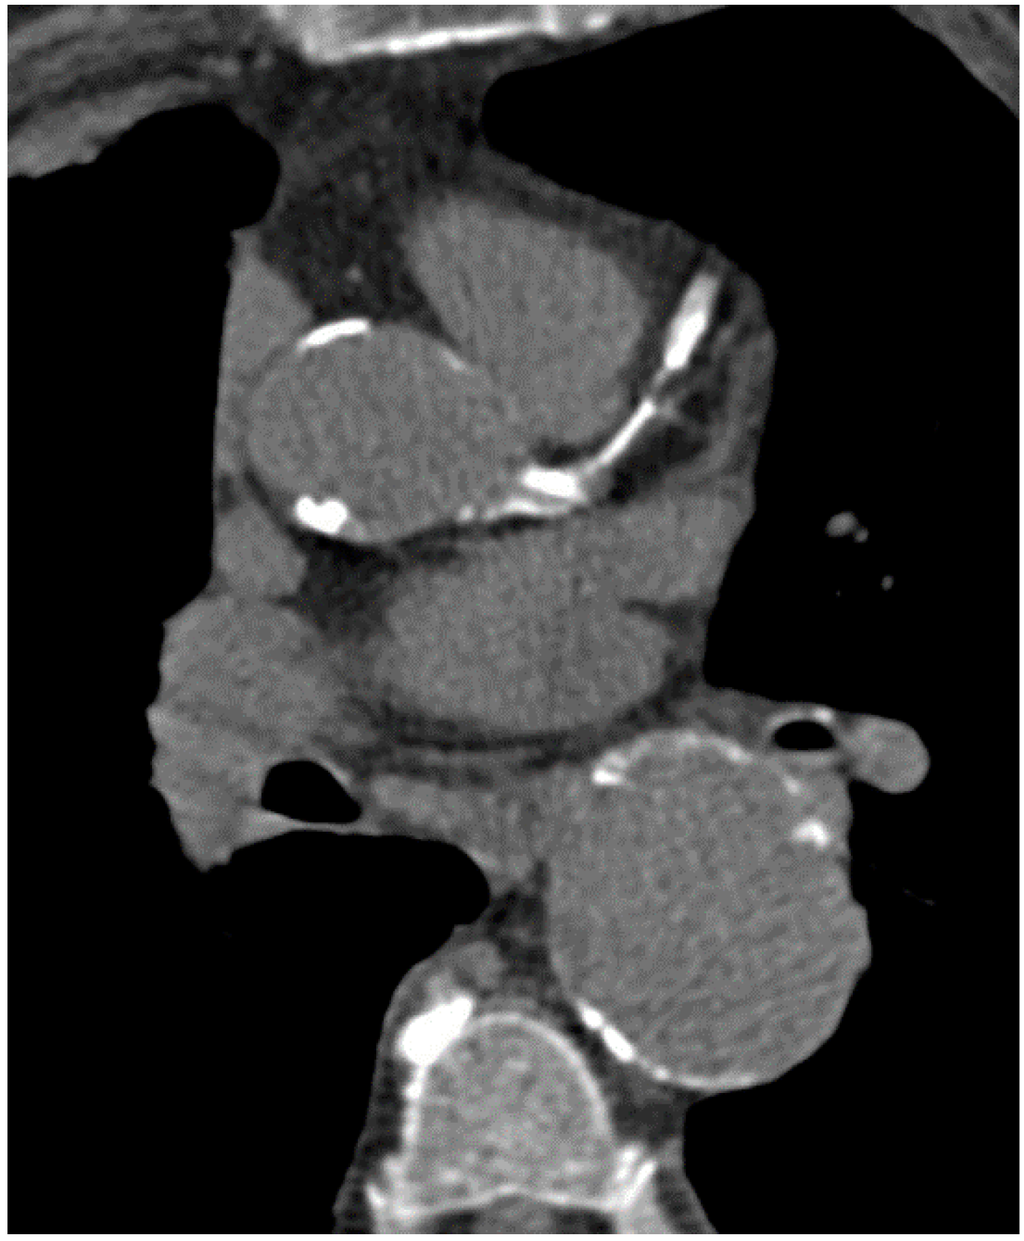

6. Imaging of Coronary Plaques and Stenoses

7. Qualitative Plaque Characterization